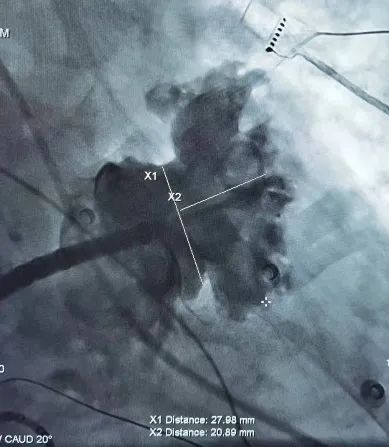

首先在患者的右侧股静脉植入11Fr及8Fr的两个鞘管,分别送入ICE导管及房间隔穿刺系统至右心房。通过对ICE的调控,选择了房间隔穿刺的最佳部位(偏下偏后)。房间隔穿刺成功后,ICE导管可以沿着导丝从右心房进入左心房的左上肺静脉。调整ICE导管后,可以从心腔内对左心耳进行测量,测量显示心耳开口24.1mm,DSA肝位造影测量心耳开口27.98mm,可用深度20.89mm,且心耳内梳状肌发达,属于典型敞口菜花型左心耳,深度极浅,手术难度颇大。考虑到心耳的形态以及稳定性,选择33mm封堵器(图4)。

图4. DSA肝位心耳造影